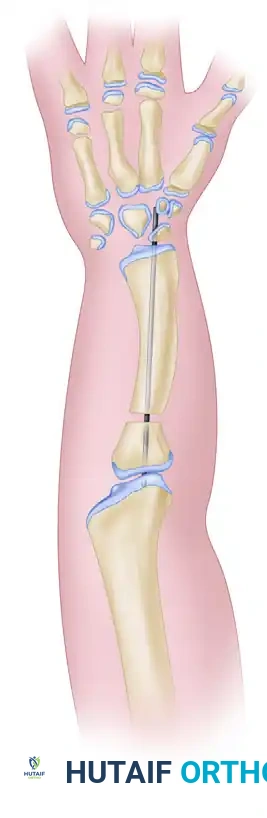

Image

Figure A: Resection of the distal ulnar anlage and the proximal radius (shaded areas).

Figure B: Alignment of the distal radius and proximal ulna to create a single osseous strut.

• Fix the construct rigidly. Pass a stout Kirschner wire (or Steinmann pin) antegrade through the olecranon, across the osteotomy site, and distally into the radial segment and carpus to ensure absolute stability.

Figure C: Kirschner wire extending into the carpals, used to stabilize the newly created radioulnar segment.

Composite Diagram: Creation of a one-bone forearm demonstrating resection, alignment, and K-wire fixation.